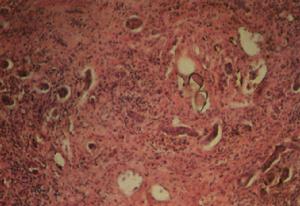

蟲卵肉芽腫是血吸蟲病的基本病理變化。現認為曼氏血吸蟲蟲卵肉芽腫的形成是一種細胞介導的免疫反應(遲髮型變態反應),由成熟蟲卵中的毛蚴所釋放的可溶性蟲卵抗原(SEA)致敏T細胞,T細胞及其釋放的多種細胞因子在蟲卵肉芽腫形成過程中起重要作用。T細胞亞型Th1細胞釋放的IL-2和IFN-γ,Th2細胞釋放的IL-4、IL-5和IL-10,巨噬細胞釋放的TNF-2和IL-1以及其細胞因子。日本血吸蟲蟲卵肉芽腫在某些方面與曼氏血吸蟲相似,但有許多獨特之處:日本血吸蟲蟲卵量為曼氏血吸蟲的10倍,蟲卵多成簇地聚集在宿主組織內,而曼氏血吸蟲蟲卵則多單個沉著;急性期肉芽腫易液化呈膿腫樣損害,浸潤細胞多以多形核白細胞為主;在肉芽腫中可見較多的漿細胞。由於大量蟲卵在組織內成堆沉積,故所形成的肉芽腫較大,其周圍細胞浸潤亦多。急性血吸蟲病患者血液中循環免疫複合物與嗜異抗體的檢出率甚高,故急性血吸蟲病是體液與細胞免疫反應的混合表現,而慢性與晚期血吸蟲病的免疫反應則屬於遲發性變態反應。

腦部血吸蟲蟲卵肉芽腫病變多見於頂葉與顳葉,主要分布在大腦灰白質交界處,周圍組織可伴有膠質增生和輕度腦水腫。迄今為止,屍檢與手術在腦靜脈中未發現成蟲,曼氏血吸蟲中樞神經系統損害很少見,以壓迫脊髓多見,而日本血吸蟲則以腦型多見。

感染使腦膜局限性或廣泛性形成不規則的肉芽腫淋巴細胞,漿細胞或多核巨細胞浸潤。腦呈不同程度的水腫,黴菌沿血管周圍和軟腦膜下聚集,形成多數小囊樣病灶,呈急性或慢性化膿性炎症反應,甚至形成腦膿腫或肉芽腫,多位於腦實質內,偶見腦室內。在膿腫和肉芽腫中可見大量黴菌體或菌絲。不同種類的黴菌感染,引起的病理變化也不相同,白色念珠球菌常引起小灶性化膿和肉芽腫;隱球菌早期形成膠凍樣病變,無纖維包膜,晚期則形成肉芽腫;放線菌主要形成多發性膿腫和肉芽腫,膿腫壁呈黃色,膿液含"硫磺顆粒"。慢性病程者常有廣泛腦萎縮